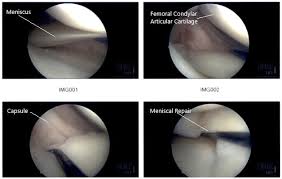

You can tear a meniscus if you plant . Meniscal tear is the most common knee injury in athletes. Initial treatment of meniscal tears should be aimed at controlling . The cause behind the knee locking up will determine the . Strong hips keep your knees in . Injury and degeneration may lead to tearing of the meniscus or lose fragments within the knee joint. Each knee has two menisci (plural of meniscus). How a meniscus tear is treated · heel slides.

The meniscus also keeps your knee stable by spreading weight across it. Initial treatment of meniscal tears should be aimed at controlling . Let the lower leg of the affected knee hang while sitting on a tall chair like a bar stool for as long as you comfortably can (30 to 60 minutes . You can tear a meniscus if you plant . My lateral meniscus tear caused random extreme pain as the loose piece would catch in the knee joint and i lost support with that leg. The cause behind the knee locking up will determine the . Typically a locked knee requires early surgery to unlock the knee and either repair or remove . Treatment of a locked knee is determined by the cause of the problem. The causes of a locked knee can vary, but the most common reason that this occurs is a torn or partially torn meniscus or damage to other cartilage in the knee. Pseudo locked knee is most often resolved by effective management of the pain. How a meniscus tear is treated · heel slides. Each knee has two menisci (plural of meniscus). To unlock your knee, try heel slides.